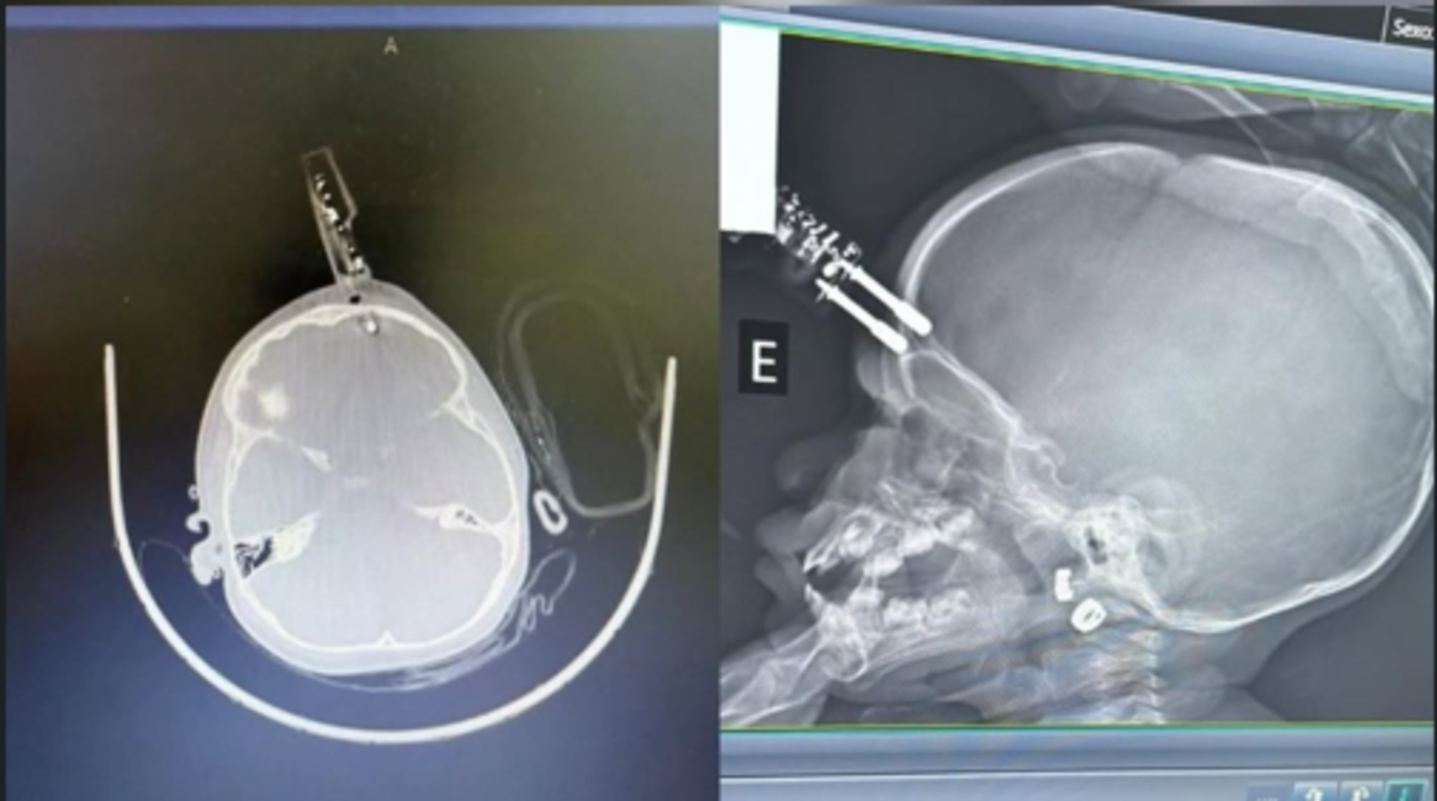

Compartilhar Facebook Twitter Email Copy Link WhatsApp Menina de 1 ano se acidentou após cair da cama enquanto a mãe estava no banheiro Fonte: